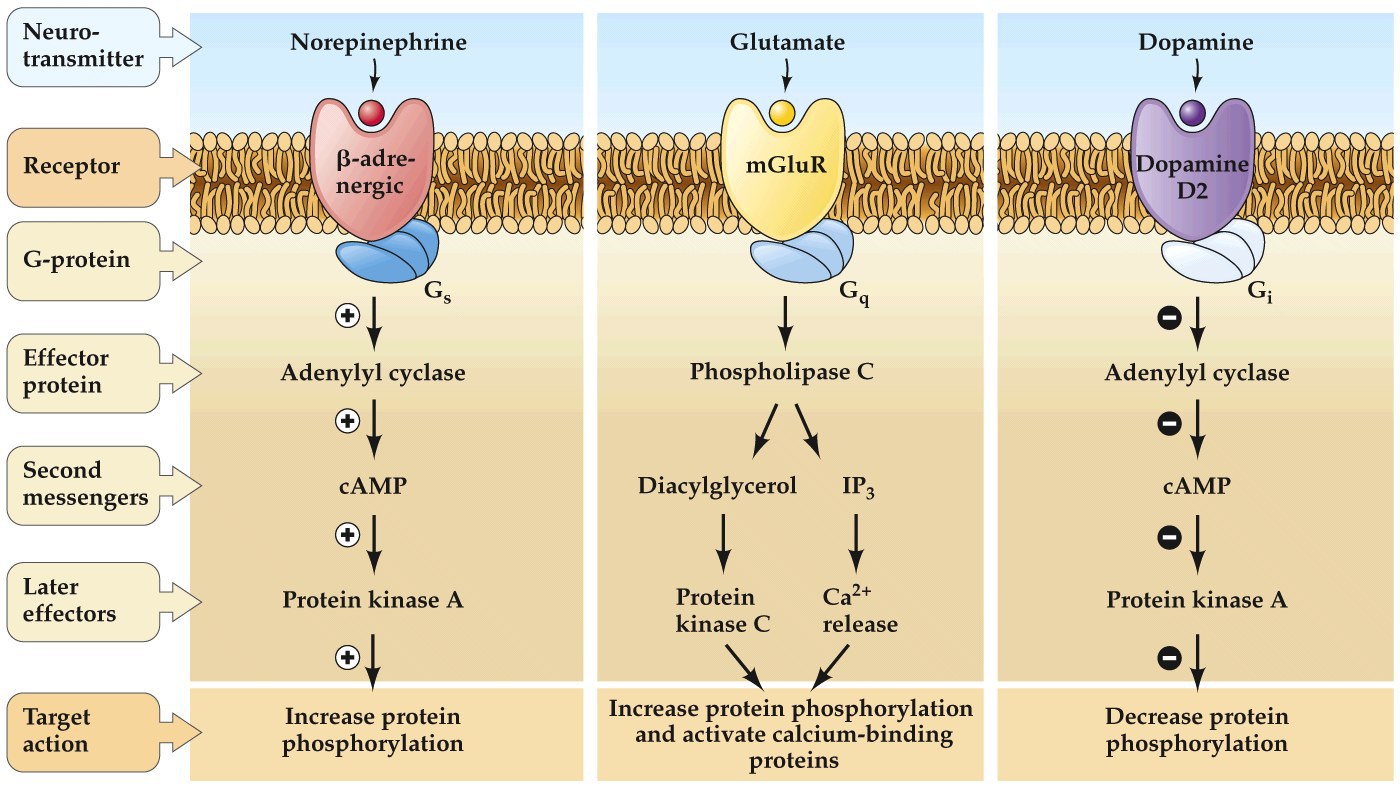

Effector pathways associated with G-protein-coupled receptors

- Those that project to GPi have type D1 receptors (coupled to a Gαs, excitatory) and those that project to GPe use type D2 receptors (Gαi, inhibitory)

Dopamine excites the direct and inhibits the indirect pathway.